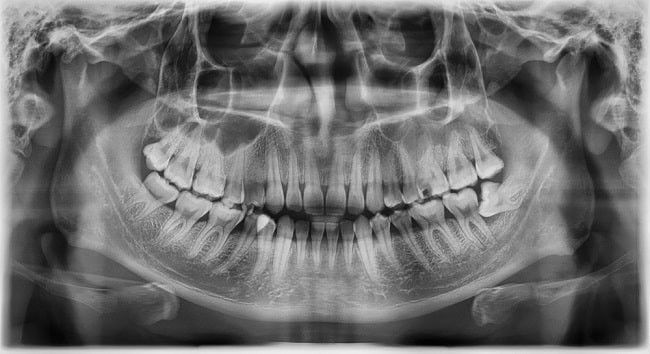

Hasil rontgen menunjukkan ada impaksi gigi (alomedika.com)